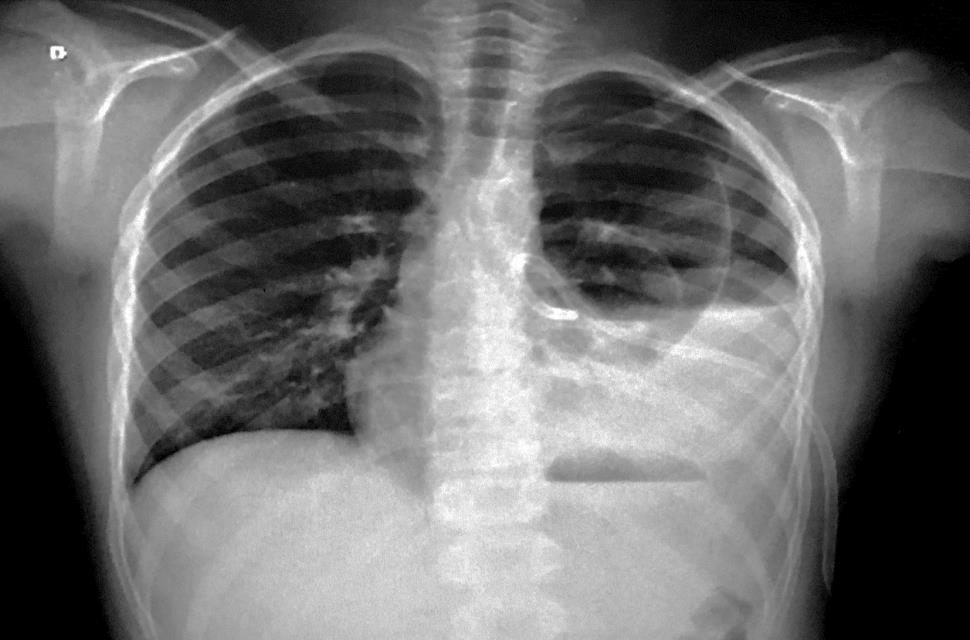

Considere a radiografia de tórax abaixo.

O diagnóstico mais provável é:

Derrame pleural.

Pneumonia em lobo inferior E.

Aumento da área cardíaca.

Derrame pericárdico.

Atelectasia pulmonar.